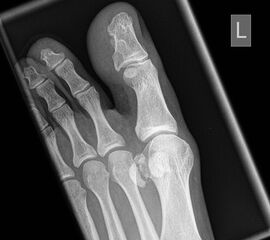

Vorfuß dorsoplantar (dp)

Positionierung:

• Patient liegt auf dem Rücken, der Fuß wird auf die Röntgenkassette aufgestellt, das Knie gebeugt.

• Der Zentralstrahl wird auf das Tarsometatarsalgelenk II zentriert.

• Die Röntgenröhre ist 15° vertikal gekippt.

• Anmerkung: Auch wenn der Fuß nicht belastet wird, sollte er auf die Röntgenkassette aufgestellt werden. Aufnahmen des hängenden Fußes sind nur eingeschränkt beurteilbar.

Kennzeichen des Röntgenbildes:

• Dorsoplantare Abbildung des Vorfußes.

• Tarometatarsale Gelenkreihe einsehbar.

• Winkelmaße können auf der unbelasteten Aufnahme des Vorfußes nicht beurteilt werden.

Besondere Bemerkungen zum Beispielbild:

• Verlaufskontrolle nach korrigierendem Vorfußeingriff bei Riesenwuchs des 2. Strahls mit verdicktem Os metatarsale II.

• Z.n. Amputation des Zehenendglieds D2.

• Z.n. Weil Osteotomie des Os metatarsale II.

• Hallux valgus interphalangeus.

Zur Vollansicht und zum Lesen der Bildbeschreibung bitte die Bilder anklicken.